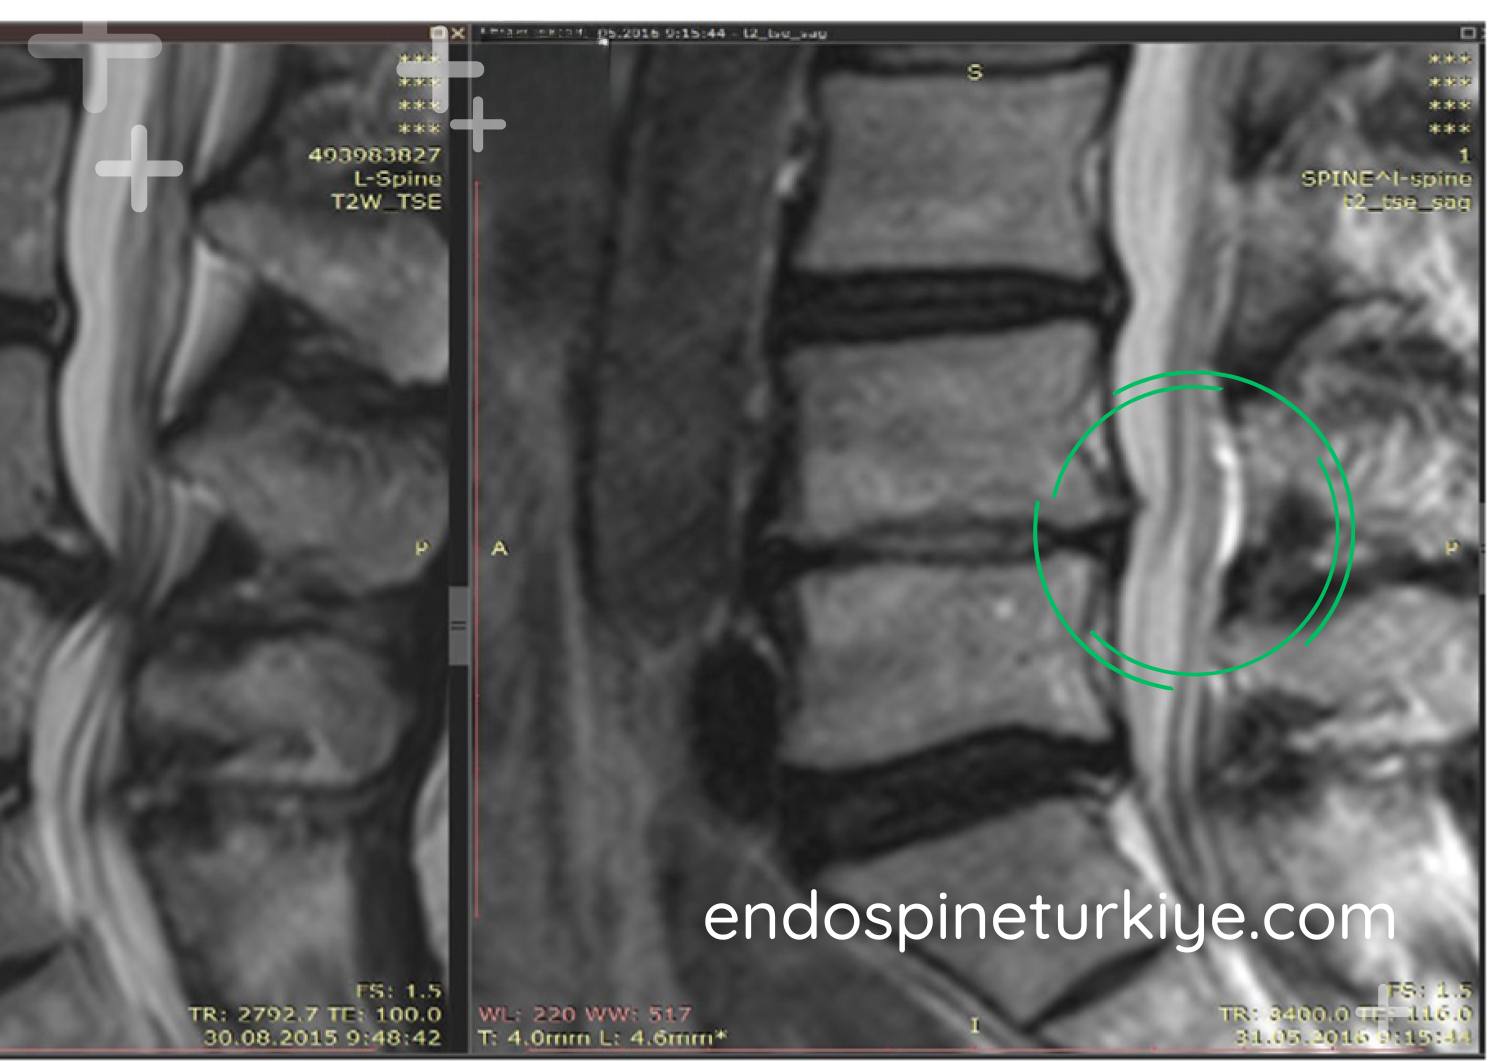

Bel Fıtığı Ameliyatı Öncesi ve Sonrası

Bel fıtığı tedavi öncesi MR görüntüsü - sinir basısı görülen lomber disk hernisi Tedavi Öncesi

Bel fıtığı tedavi sonrası MR görüntüsü - endoskopik ameliyat ile sinir basısı giderilmiş Tedavi Sonrası

MR görüntülerinde endoskopik bel fıtığı ameliyatı öncesi ve sonrası karşılaştırma